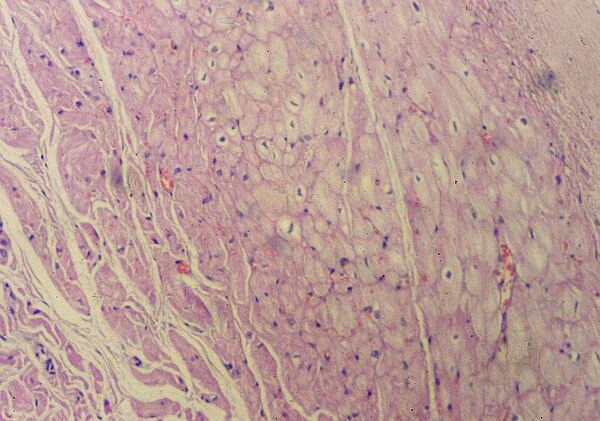

Гистологическое строение сердца

Стенка сердца состоит из трёх слоёв — эпикарда, миокарда и эндокарда. Эпикард состоит из тонкой (не более 0,3—0,7 мм) пластинки соединительной ткани, эндокард состоит из эпителиальной ткани, а миокард образован поперечно-полосатой сердечной мышцей (разновидность поперечно-полосатых мышц).

Зрелая клетка миокарда (кардиомиоцит) имеет размер до 25 μm в диаметре и 100 μm в длину. Клетка имеет поперечно-полосатую исчерченность подобно клетке скелетной мышцы. Однако, в противоположность многоядерным скелетным миофибриллам, кардиомиоциты имеют одно или два ядра, расположенных в центре клетки. Вокруг каждого кардиомиоцита присутствует соединительная ткань, богатая сетью капилляров[1].

Миокард густо пронизан кровеносными сосудами и нервными волокнами, образующими несколько нервных сплетений. На каждый капилляр миокарда приходится примерно четыре нервных волокна[B: 5].

Мембрана миокардиальных клеток называется сарколеммой. Особый участок мембраны представлен вставочным диском — это отличительная характеристика ткани сердечной мышцы. Вставочные диски через обычный микроскоп видны как темно окрашенные поперечные линии, которые через неравномерные промежутки пересекают цепочки сердечных клеток. Диски представляют сложные мостики, соединяющие соседние волокна сердца, образуя структурную и электрическую непрерывную связь между клетками миокарда. Для обслуживания огромных метаболических потребностей сердца и обеспечения высокоэнергетическими фосфатами, миокардиальные клетки снабжены изобилием митохондрий. Эти органеллы расположены между отдельными миофибриллами и занимают приблизительно 35 % объёма клетки[1].

Гистологический микропрепарат мышечной ткани сердца. Оптическая микроскопия, ×100, окраска гематоксилин-эозином